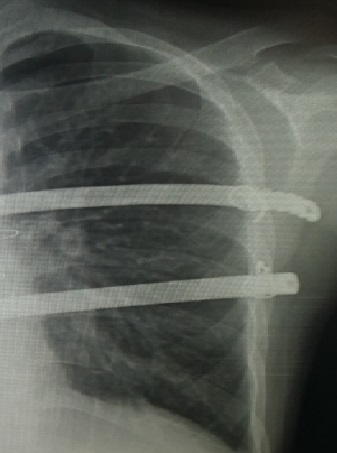

一些做了胸廓畸形手术的朋友会出现钢板两端露出皮表的情况(图1)。这样的情况一旦出现,会令患者非常不安,唯恐出现大问题。为什么会出现这样的情况呢?可能与如下几个因素有关。

图1,钢板从切口露出体表,局部渗出并感染,严重影响康复质量。

其次,钢板两端形状的问题(图2,3,4)。钢板放入体内前,要对钢板进行满意的塑形,使之不但能起到支撑或者压迫的作用,还要与胸廓自然形状相适应,不能使两端翘得太高。两端翘得过高,皮肤表面就可能被顶起来。当皮肤被衣服或者外界因素摩擦时,可能轻易被磨破而导致钢板外露。

图2,钢板两端翘起,很容易顶破皮肤而造成钢板外露。

图3,钢板几乎要破皮而出,该患者的钢板放置存在严重问题。